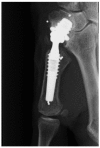

Adverse reactions to metal-on-metal (MoM) prostheses are well known from total hip joint resurfacing arthroplasty with elevated serum chrome or cobalt, pain and pseudo tumor formation. It may, however, also be seen after total joint replacement of the trapeziometacarpal joint using MoM articulation, and we present two cases of failure of MoM prostheses due to elevated metal-serum levels in one case and pseudo tumor formation in another case. Furthermore, we suggest a diagnostic algorithm for joint pain after MoM trapeziometacarpal joint replacement based on published experiences from MoM hip prostheses and adverse reactions to metal.